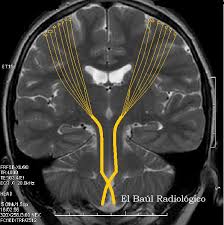

Amyotrophic lateral sclerosis is a neurodegenerative neuromuscular disease that results in the progressive loss of motor neurons that control voluntary muscles. Posterior and lateral walls of duodenal bulb penetrate first of all to the head of the pancreas, more rare in large ducts of biliary tract, liver, ligaments (gastrohepatic or duodenal). La esclerosis lateral amiotrófica es una enfermedad progresiva y de mal pronóstico que provoca debilidad de los. Se origina cuando las células del sistema nervioso llamadas motoneuronas disminuyen gradualmente su funcionamiento y mueren. La esclerosis lateral amiotrófica, o ela, es una enfermedad progresiva del sistema nervioso que afecta las células nerviosas en el cerebro y la médula espinal, y causa pérdida del control muscular.

• la esclerosis lateral amiotrófica (ela) es una enfermedad crónica y degenerativa del sistema nervioso, que se caracteriza por la muerte progresiva de las motoneuronas.

La esclerosis lateral amiotrófica es una enfermedad que causa pérdida progresiva de la fuerza y atrofia de los músculos, llevando a la muerte en cerca de 3 a 5 años. A als, o esclerosis lateral amiotrófica, es una enfermedad de las partes del sistema nervioso que controlan el movimiento de los músculos voluntarios. La palabra amiotrófica significa sin nutrimento. La esclerosis lateral amiotrófica (ela) es una enfermedad del sistema nervioso central caracterizada por una degeneración progresiva de las neu­ ronas motoras en la corteza cerebral. Esta pagina es confines educativos.

La esclerosis lateral amiotrófica (ela) es una enfermedad del sistema nervioso central caracterizada por una degeneración progresiva de las neu­ ronas motoras en la corteza cerebral.